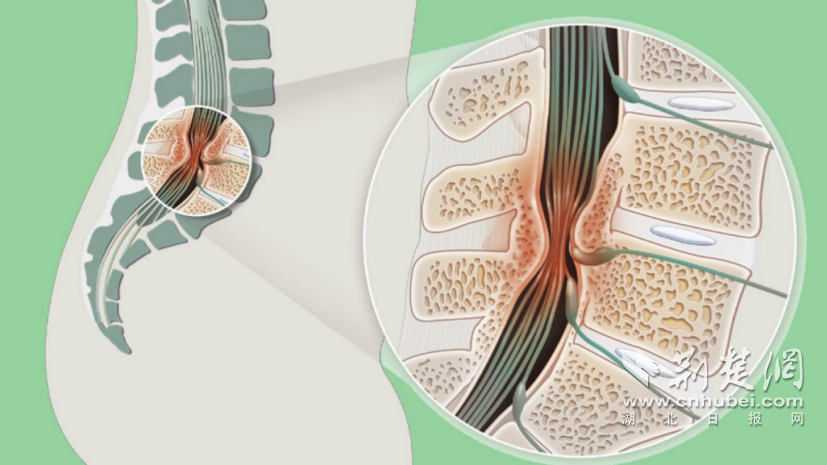

女子腹痛竟是胃“移位”入胸腔 医生巧补“破洞”让胃安全归位

她未曾想到,自己胸腔与腹腔之间的屏障——“膈肌”竟出现了两处破洞,导致三分之二的胃体“闯入”胸腔。[查看全文]